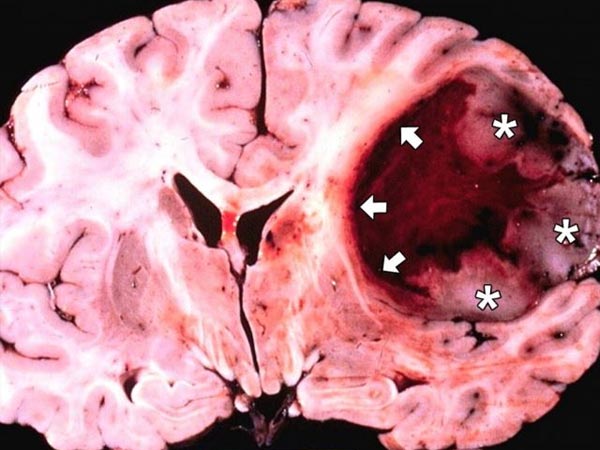

ग्लियोब्लास्टोमा मल्टीफॉर्म या जीबीएम एक प्राणघातक ब्रेन ट्यूमर है जो कि व्यस्कों में पाया जाने वाला घातक मलिग्नैंट प्राइमरी ब्रेन ट्यूमर है। इसे एस्ट्रोसाइटोमा ग्रेड IV की श्रेणी में रखा जाता है। GBM, का विकास स्टार के आकार वाली कोशिकाओं की लीनीऐज से होता है, जिसे एस्ट्रोसाइट्स कहते है। यह कोशिकाएं, तंत्रिका कोशिकाओं को समर्थन प्रदान करती है।

GBM मुख्य रूप से सेरिब्रल हेमिस्फेरेस में विकसित होती है, लेकिन यह ब्रेनस्टेम, रीढ़ की हड्डी या ब्रेन के अन्य भागों में भी विकसित हो सकता है।